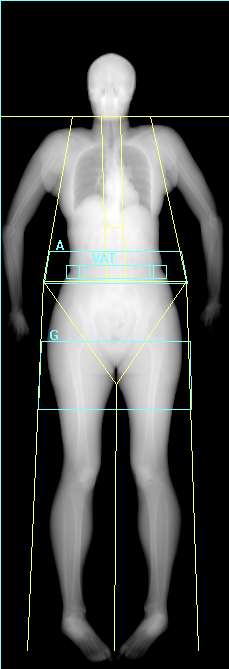

DEXA Scan Visceral Fat

Fat

Lean

Bone

Visceral fat, sometimes called "spillover" fat, builds up around internal organs like the liver and pancreas once subcutaneous fat stores are full.

While some is protective, too much increases the risk of heart disease and diabetes.

A healthy measurement for you would be < 100cm².

Your Visceral fat measurement is 58.8cm²

Normal risk for metabolic disorders, cardiovascular diseases

Normal

Increased

High

20cm²

100cm²

160cm²

Compared to others the same age and sex

0/100 - Compared to other 39 year old females.